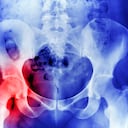

La osteoporosis es una enfermedad que se caracteriza por una disminución de la densidad de los huesos como consecuencia de la pérdida del tejido óseo normal, lo que hace que se vuelvan más frágiles y se fracturen con facilidad. Los más susceptibles a esta situación son los de la cadera, la muñeca o la columna vertebral.

De acuerdo con los expertos, los huesos frágiles y quebradizos pueden ser causados por cualquier cosa que haga que el cuerpo destruya demasiado hueso o que evite que forme suficiente nuevo. Por ejemplo, a medida que las personas envejecen, el cuerpo puede reabsorber calcio y fosfato de los huesos, en lugar de mantener estos minerales en ellos, generando debilidad en los mismos.

- Antecedentes familiares. Tener un padre, madre o hermano con esta enfermedad genera mayor probabilidad de desarrollala, especialmente si la madre o padre sufrieron fractura de cadera.